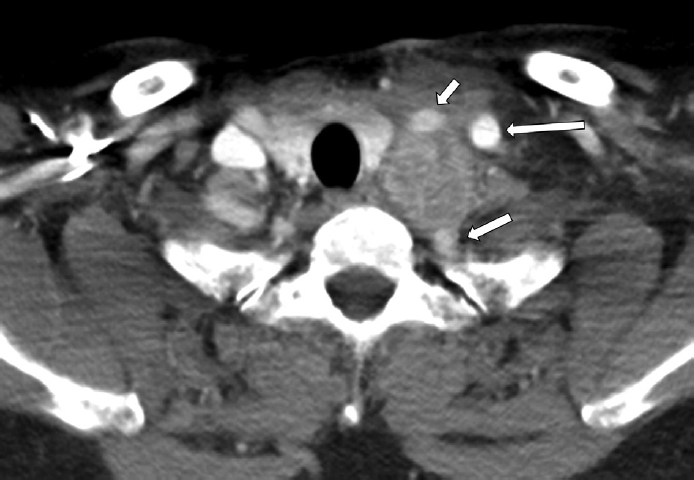

On neck computed tomography, an approximately 3.5 cm, oval to round mass with heterogeneous contrast enhancement was observed in the left upper mediastinum (Fig. 1). The lesion widened the interval between the common carotid artery, internal jugular vein, and subclavian artery and appeared adherent to the common carotid and subclavian arteries. Opacification obstructing the left maxillary sinus and both anterior ethmoid sinuses was also noted, raising suspicion of sinusitis. On upper airway endoscopy, there were no remarkable findings in the larynx or upper trachea, vocal cord mobility was good bilaterally, bilateral nasal polyps were observed, and mucopurulent discharge was present in the left middle meatus.

Neck CT demonstrates a 3.5 cm sized somewhat elliptical somewhat round heterogeneously enhanced mass in the left upper mediastinum between the space of common carotid artery (short arrow), internal jugular vein (long arrow), and subclavian artery (middle sized arrow), adhered into the common carotid and subclavian artery.